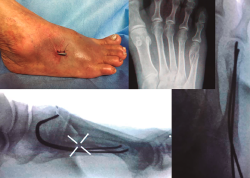

Figura 3. Sexto paciente objeto de nuestro estudio, masculino, de 21 años, que sufre fractura en 3.º, 4.º y 5.º metatarsianos por traumatismo directo en accidente de motocicleta. En sentido horario empezando arriba a la izquierda: radiografía preoperatoria, radiografías postoperatorias a la tercera semana (proyecciones anteroposterior y lateral en apoyo), aspecto del pie al finalizar el procedimiento quirúrgico.

En las Figuras 3 y 4 se presentan los resultados postoperatorios de los pacientes incluidos en nuestro estudio.